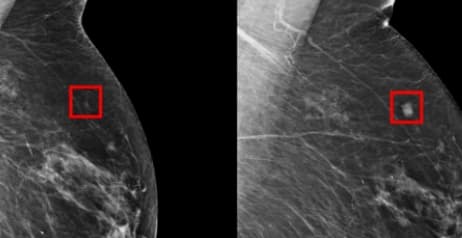

Forskare vid MIT-universitetet i Boston har tagit fram ett AI-baserat system som kan förutspå huruvida en patient ligger i riskzonen för att utveckla bröstcancer. Det rapporterar Engadget.

Den artificiella intelligensen har tränats genom att få analysera mammografibilder på över 60 000 patienter. De som utvecklat bröstcancer inom en femårsperiod från det att mammografibilderna togs har flaggats, och systemet har på så vis lärt sig leta efter tidiga tecken på sjukdomen.